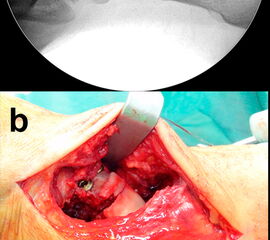

Frakturen des Proc. fibularis tali werden im konventionellen Röntgenbild nicht selten übersehen. Sie entstehen häufig nach schweren Distorsionen bzw. im Rahmen subtalarer Luxationen. Eine CT-Kontrolle nach geschlossener Reposition subtalarer Luxationen ist daher obligat (Ab. 15). Der Proc. fibularis tali ist über den anterolateralen Zugang oder schräg verlaufenden Ducroquet-Ollier-Zugang gut zu erreichen. Die subtalare Arthroskopie über anterolaterale und posterolaterale Portale bietet wie bei intraartikulären Kalkaneusfrakturen die Möglichkeit der exakten Kontrolle der geschlossenen Reposition bei einfachen Frakturformen 35. Nach anatomischer Reposition und temporärer Fixierung mittels 1,0 Kirschnerdraht erfolgt die Osteosynthese mittels Kleinfragmentschrauben (2,7 bzw. 3,5 mm), die unterhalb der Knorpel- Knochengrenze eingebracht werden und für eine ausreichende Stabilität sorgen (Abb. 16). Kleinere, nicht anatomisch refixierbare Fragmente, oder Fragmente mit starker Knorpelkontusion werden vorzugsweise exzidiert (Abb. 17). Gleiches gilt für Frakturen des Proc. posterior tali zur Vermeidung einer posttraumatischen Arthrose 23736.

Zur Vollansicht und zum Lesen der Bildbeschreibung bitte die Bilder anklicken.